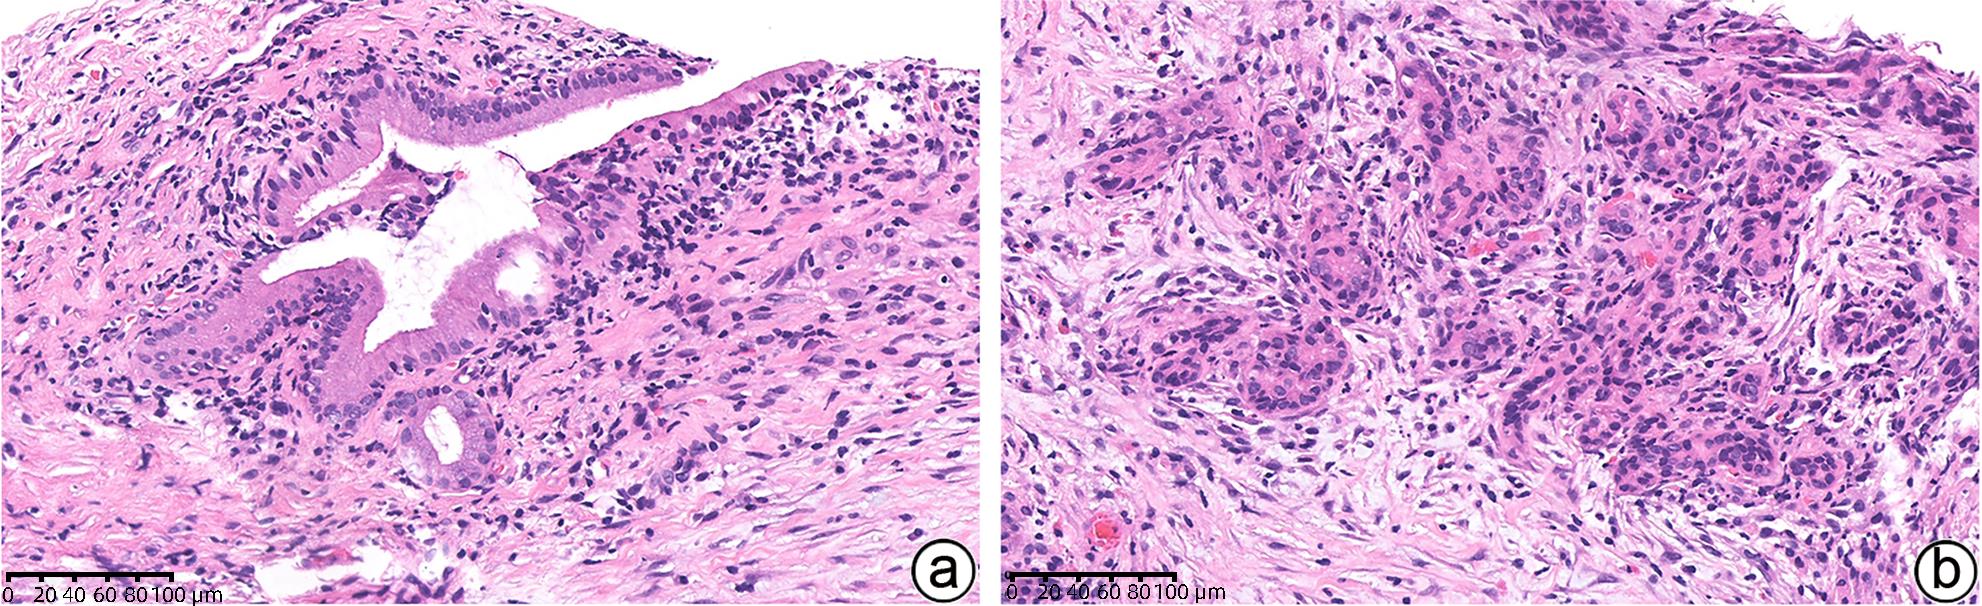

Pathological diagnosis of autoimmune pancreatitis

Ke SUN

2024, 40(6): 1100-1106. DOI: 10.12449/JCH240606

Abstract(1537) HTML (341) PDF (1309KB)(147)

Abstract:

Autoimmune pancreatitis (AIP) is a rare disease, and its diagnosis should be made based on a comprehensive evaluation of clinical, radiological, serological, and pathological findings. At present, AIP is classified into two subtypes of type 1 (identified as the pancreatic manifestation of IgG4-related disease) and type 2 (identified as the pancreas-specific disorder independent of IgG4). Although type 1 and type 2 AIP seem to have different pathogeneses, they tend to have similar radiological findings and exhibit a good response to corticosteroid therapy. This article mainly reviews the histopathological features of the two subtypes of AIP, especially the diagnostic challenges encountered in the interpretation of specimens obtained through endoscopic ultrasound-guided fine needle aspiration/biopsy, to as to help pathologists enhance the accuracy of the diagnosis of AIP.